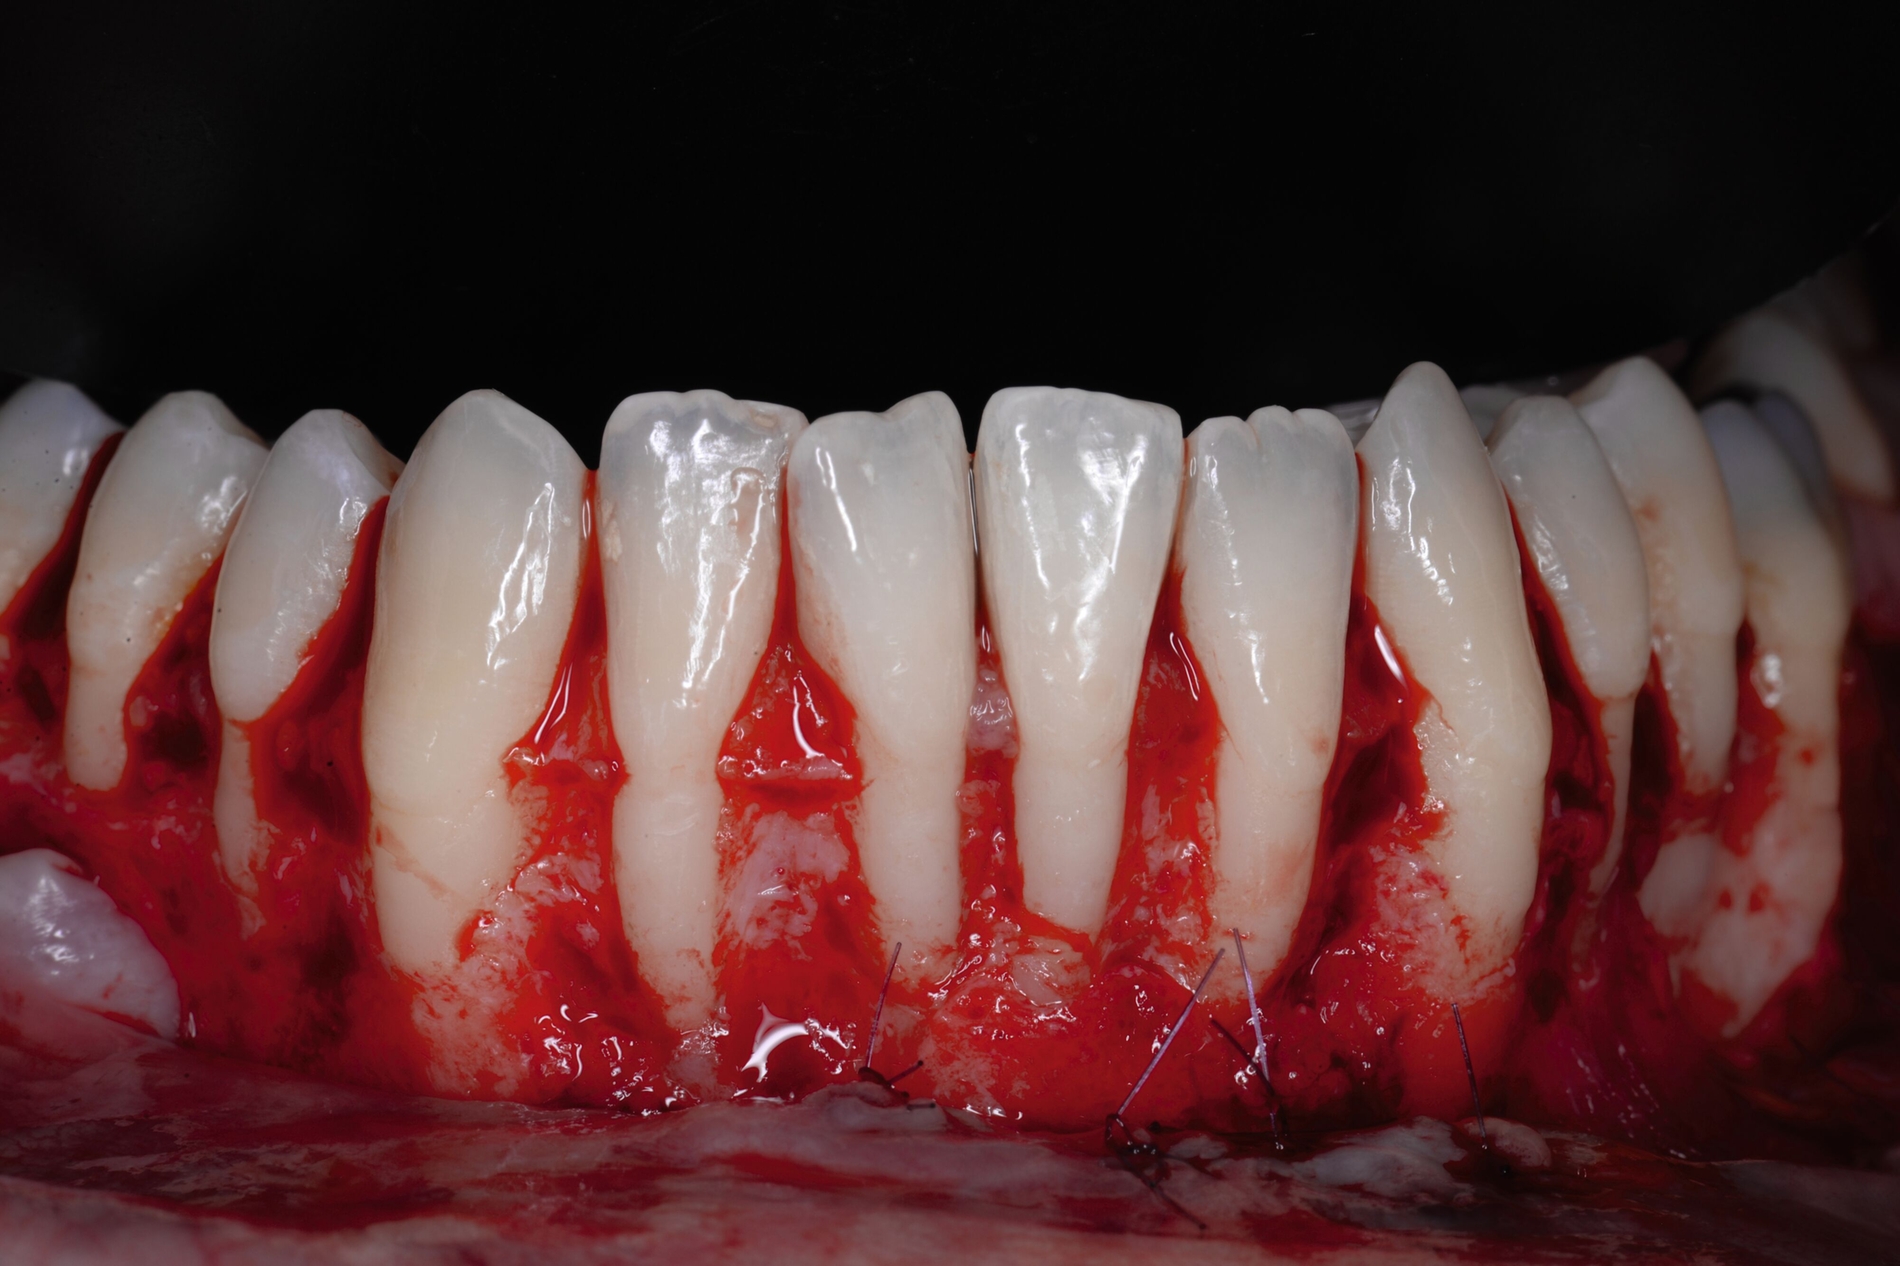

Beim lateralen Verschluss der tiefen Rezession im Rahmen der LCAT- oder LCAF-Technik ist immer mit dem Auftreten von Spannungen zu rechnen, insbesondere wenn die Rezession eine deutliche Breite aufweist. Nicht möglich ist dieses entlastungsinzisionsfreie Vorgehen, wenn mehrere tiefe Rezessionen direkt oder unmittelbar benachbart sind, da dann das Gewebe in die entgegengesetzte Richtung lateral mobilisiert werden müsste. Für diese Patienten haben Tunkel et al. eine Methode entwickelt, die grundsätzlich die Prinzipien der Koronalverschiebung nach Zucchelli, die Nelson-Technik und die LCAF-Technik verbindet und versucht, deren Vorteile zu kombinieren und deren Nachteile zu kompensieren: den „Mehrfach Gestielten Koronal Verschobenen Lappen“ (MPCAF) [Tunkel et al., 2021; Tunkel et al., 2022] (Abbildung 4). Gleichzeitig ist es damit möglich, mehrere auch direkt nebeneinander liegende Rezessionen zu decken.

Dabei wird zunächst – wie bei der LCAF-Technik – die Gingiva der tiefen Rezessionsareale exzidiert und die Inzision in gleicher Weise horizontal erweitert (Abbildung 4b). Zum Ende des gewünschten Präparationsareals wird aber eine vertikale Entlastungsinzision gezogen. Hier gibt es aber deutliche Unterschiede zur Nelson-Technik: Die Inzision liegt durch die horizontale Erweiterung weiter von der tiefsten freiliegenden Wurzeloberfläche entfernt und wird bei multiplen Rezessionen auch möglichst in den Seitenzahnbereich verlegt, damit die daraus resultierenden Narben später nicht sichtbar werden. Zudem wird die Rezession nicht gerade, sondern in einem runden Rückschnitt geführt, so dass zur Lateralisation keine Verschiebung, sondern eine Rotation durchgeführt werden kann, was trotz der seitlichen Verlagerung eine Deckung des Areals der Entlastungsinzision ermöglicht.

Jetzt wird beginnend an einer Seite der erste Lappenanteil nach dem Prinzip teilschichtig-vollschichtig-teilschichtig gelöst und im Bereich der ersten tiefen Rezession mittels feiner monofiler Nähte mit dem proximalen Lappenanteil vernäht. Dieser wird daraufhin gelöst und bei der nächsten tiefen Rezession erneut mit dem nahe gelegenen Lappenanteil verbunden. Dieser Vorgang wird fortgeführt, bis so erneut ein großer gesamter Lappen entstanden ist, der koronal verschoben werden kann (Abbildung 4c). Das weitere Vorgehen ist exakt wie bei der LCAF-Technik: Entepithelialisierung der Papillenareale, Gewinnung des Transplantats, Applikation von EDTA-Gel und Schmelz-Matrix-Proteinen, Fixation des Transplantats und Fixierung des Lappens nach koronal (Abbildungen 4d bis 4f). Die runden Entlastungsinzisionen lassen sich meist ohne größere Mühe verschließen, selbst wenn multiple tiefe Rezessionen vernäht worden sind.

Der MPCAF ist neben der von Bernimoulin beschriebenen Methode eine von nur sehr wenigen Techniken, mit der multiple tiefe RT1-Rezessionen gedeckt werden können. Allerdings kann eine vollständige Narbenfreiheit nicht gewährleistet werden. Daher ist es zu empfehlen, bei dieser Technik den Lappen mindestens bis zum Eckzahn oder ersten Prämolaren auszudehnen. Eine Überdeckung von mehr als 2 mm der Schmelz-Zement-Grenze ist möglich, so dass eine hundertprozentige Deckung erreichbar ist. Allerdings ist aufgrund der Verschiebung und des Vernähens mehrerer kleiner Lappenanteile die Methode äußerst techniksensibel und daher nur erfahrenen Anwendern zu empfehlen.